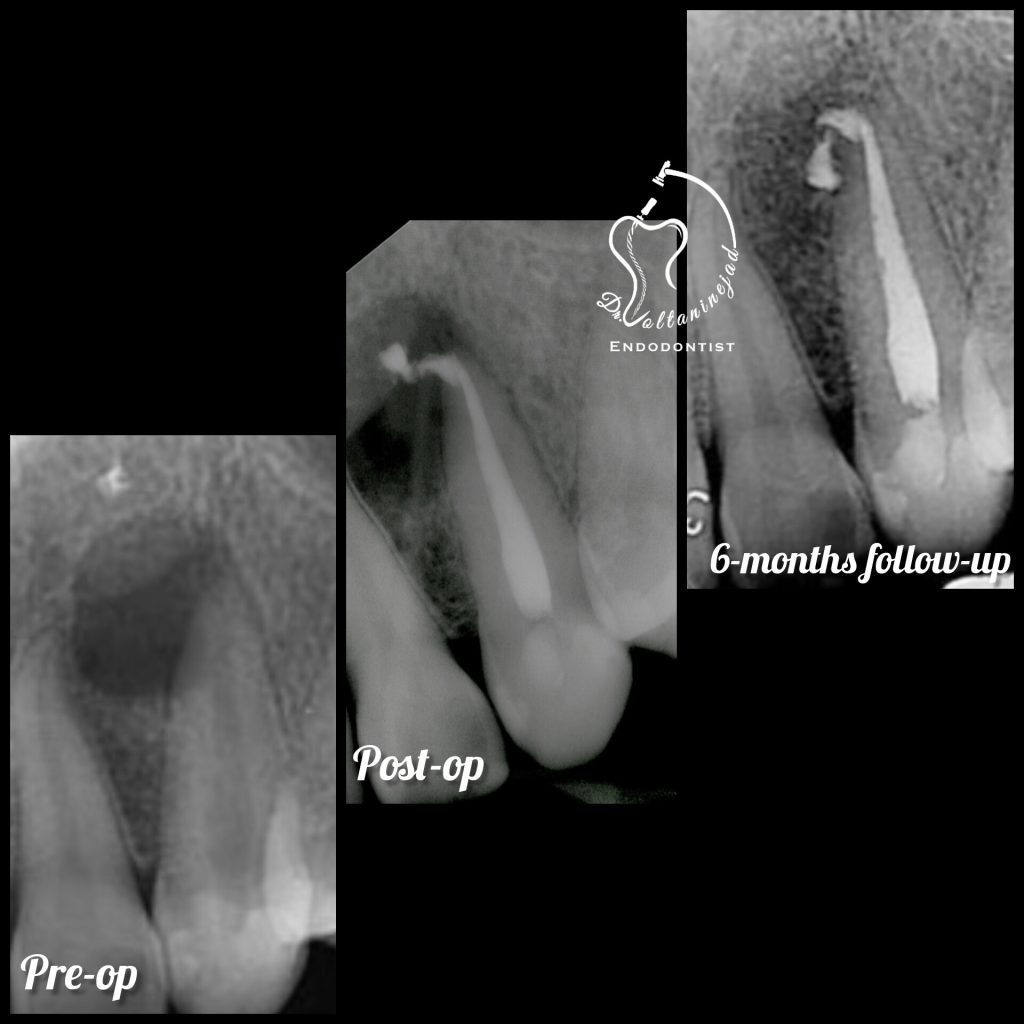

🔹 درمان ریشه مجدد (Retreatment) در دندان پرمولر

• شرح کوتاه: درمان قبلی نامناسب و همراه با عفونت بود. درمان مجدد با میکروسکوپ انجام شد.

• نتیجه: ترمیم ضایعه استخوانی و بازگرداندن دندان به شرایط سالم.

درمان ریشه مجدد پرمولر